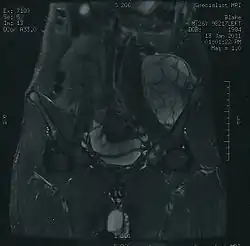

Las localizaciones más frecuentes son pelvis, costillas, fémur y húmero.